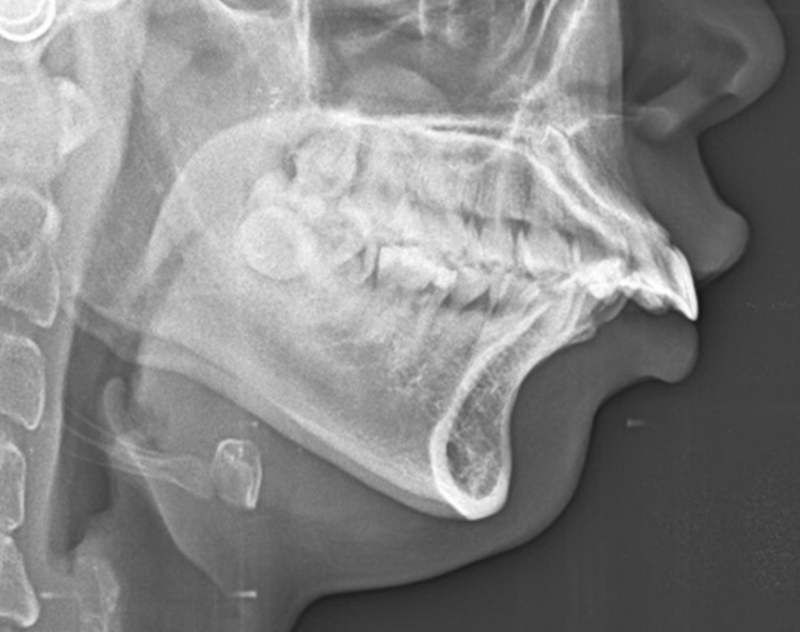

上颚骨太长或是太突出时,因为上排牙齿的位置跟着改变,可能会导致笑的时候牙龈整个露出来,这样的笑容比较不吸引人。

'' 严重的案例,甚至闭嘴时嘴唇无法完全盖住牙齿,因此平常在人前都要刻意闭紧嘴唇,看起来比较严肃不易亲近。

'' 正颚手术可以调整上颚骨的位置,因此可以改善微笑时牙龈外露的问题。在这个案例中我们将上颚骨往上移动并且制造一点点前倾的角度,因此改善了牙龈外露的困扰,同时也可以创造出迷人的微笑曲线。